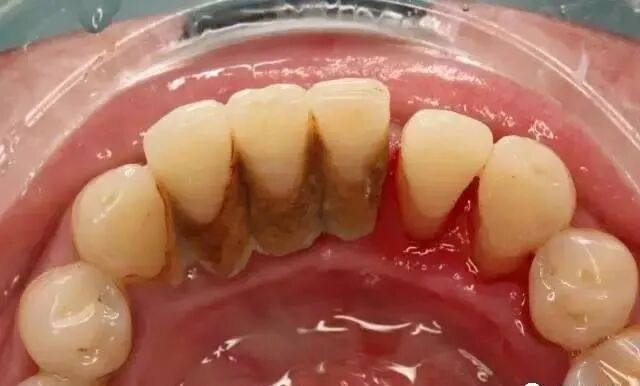

(洁牙前)

刷牙用牙线可以去除牙齿表面及牙间隙的污垢,可是,即使是每天定时正确刷牙和用牙线,仍然会有30%左右软垢躲藏在隐蔽角落无法清理干净。久而久之,含有大量细菌的软垢和唾液中矿物质结合逐渐变硬成为牙结石。细菌是导致牙龈炎的、牙周病的罪魁祸首,虽然牙结石本身是已经坏死的细菌并不会引起牙龈炎。

事实上,只有专业洗牙才会彻底清除普通刷牙无法去除的牙结石,细菌毒素及牙齿表面沉积的色素。同时,定期洗牙也会尽早发现不易察觉的牙病,及时消除隐患。

有些人担心洗牙后牙缝会变大。其实这是多年口腔卫生习惯不好所造成的后果,当牙石堆积在牙齿周围,附着其上的牙菌斑释放毒素导致牙周围的牙槽骨吸收,牙间隙变大,增大的牙缝又被更多的牙结石和肿胀的牙龈填满。当牙结石被去除,牙龈消肿后,早已存在的牙缝自然会显露出来。

对牙周病的患者,洗牙之前堆积在牙齿周围的牙结石就像小夹板一样将已经松动的牙齿箍在一起,当刚刚去掉牙结石,牙龈尚未恢复健康之前,就有可能感到牙齿松动,牙周病越严重,牙槽骨吸收越多,松动越明显。对轻中度牙周病患者,洗牙后炎症消退,牙龈更加坚实地附着在牙周,牙齿松动也会得到改善。